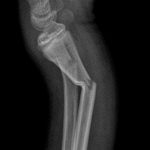

Essa transformação não está apenas nos números. Ela pode ser vista. As imagens que acompanham este texto mostram dois casos atendidos hoje no pronto socorro: crianças com fraturas no antebraço que foram avaliadas, diagnosticadas e operadas no próprio hospital, sem necessidade de transferência. Situações que exigem agilidade, equipe treinada e estrutura funcional.

Em outro episódio recente, uma criança em férias na cidade, com fratura grave de cotovelo, passou por todo o processo, do atendimento à alta hospitalar, em cerca de 10 horas, e já recuperada enviou um vídeo de agradecimento diretamente de Portugal, há dois dias.